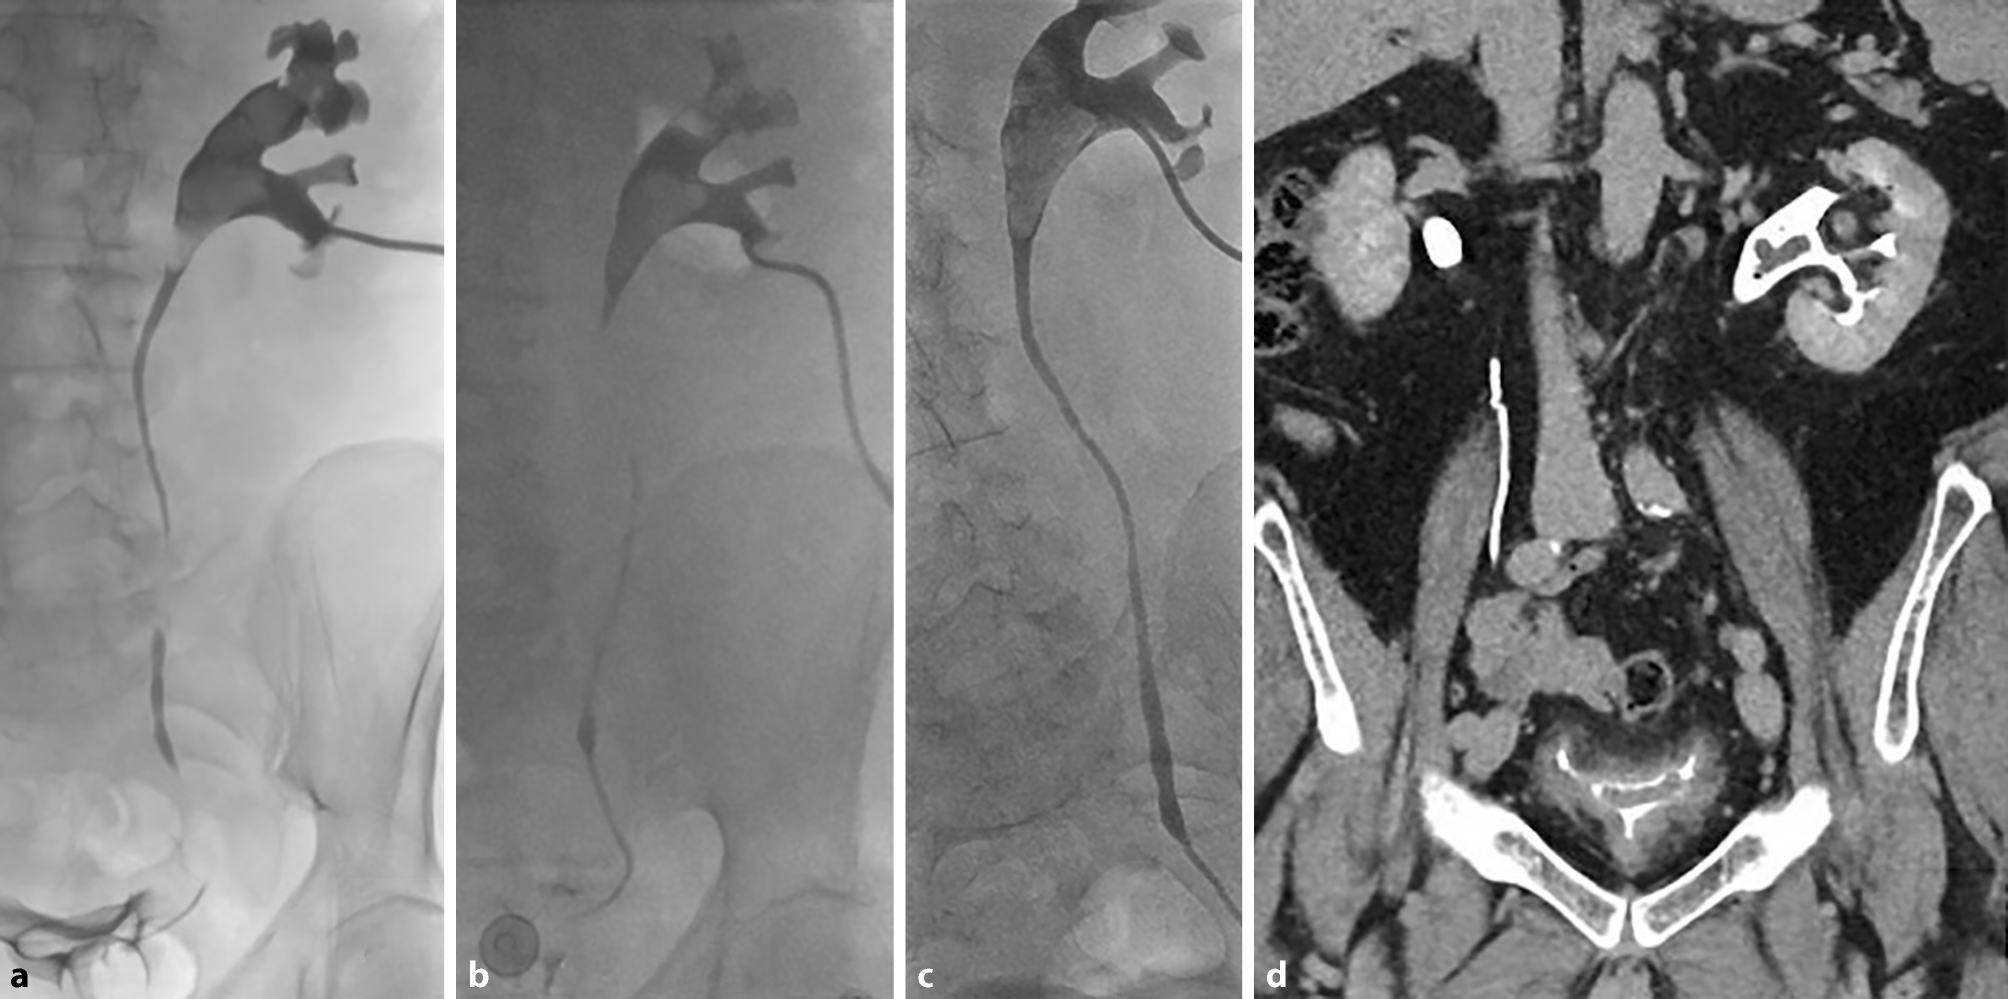

De behandeling leverde wisselende resultaten op (fig. 3), maar bij evaluatie na negen weken intrapyelische spoelingen bleek er een beduidende toename te zijn en werd besloten dat er sprake was van onvoldoende broncontrole. Er werd een nieuwe evaluatie van disseminatie uitgevoerd met FDG-PET/CT, fundoscopie en een transoesofageaal echocardiogram, die geen strooihaarden aantoonde. Bijgevolg werd besloten tot operatief ingrijpen om de fungal balls te verwijderen. De spoelingen werden tot aan de operatie nog vervangen door anidulafungine (50 mg/l). Vierentwintig uur preoperatief werd meropenem en caspofungine gestart ter dekking van respectievelijk eerdere ESBL en Candida albicans. De fungal balls konden volledig en succesvol worden verwijderd met robotgeassisteerde pyelo- en cystotomie (fig. 4).

Figuur 3

Antegrade pyelografie. Resultaat na 2 weken (a), na 4 weken (b), na 9 weken (c en d) intrapyelische spoeling met amfotericine B

Figuur 4

Operatieve verwijdering van de fungal ball. a en b verwijdering fungal ball met pyelotomie; c verwijdering fungal ball met intraperitoneale cystotomie; d fungal balls na verwijdering